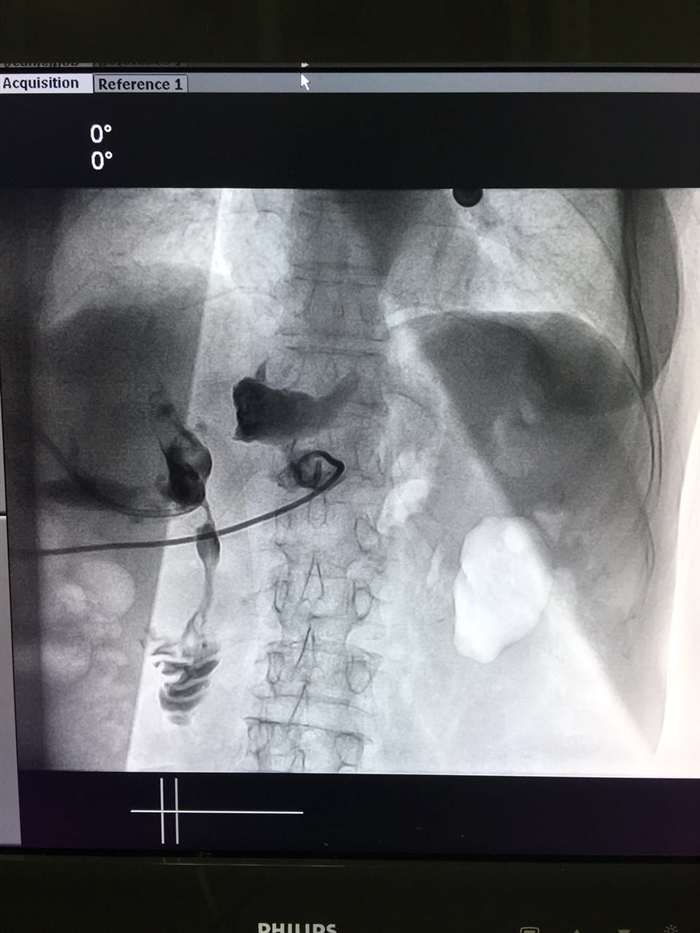

6月29日晚上7点,肝胆外科在龚建平主任指导下及泌尿外科姜庆主任的鼎力协助下,由留美归来的刘作金副主任主刀,程瑶博士为助手,历时4小时,为一例反复多次手术的肝内外充满型胆管结石伴严重肝硬化的患者成功完成了经皮经肝胆道造瘘联合经皮肾镜碎石取石术。该手术采用杂交手术的方式完成,先于B超下定位穿刺目标胆管,随后于介入中心逐次扩张胆管并置入合适直径外鞘。再将患者移入普通手术室在全麻下经扩张隧道用经皮肾镜碎石。此手术在西南地区尚属首例。术后患者病情稳定,于2016年7月6日恢复出院。

62岁的女性患者熊某,因“反复腹胀、皮肤巩膜黄染4月,胆道探查术后1月”入院。此患者既往因广泛肝内外胆管结石导致胆汁淤积性肝硬化,继发重症胆管炎感染中毒性休克,与1月前行急诊下行胆道探查术引流手术。因无法解决广泛沉积的肝内胆管结石梗阻,即使此后补行的超声引导下的的经皮肝胆管穿刺置管造瘘术(PTCD),也因肝内胆道充满结石而效果不佳,胆道梗阻无法有效缓解。类似熊某的这种病情并非罕见,尤其是位于肝内、外胆管结石的高发的西南地区。此类患者不仅肝内胆管结石多、而且位置高、还多伴随胆管狭窄及胆汁淤积性肝硬化,并常有反复多次胆道手术病史,腹腔粘连极其严重。传统开腹手术不仅创伤大和并发症高,而且术后结石残留率高,对充满型肝内胆管结石等复杂病例甚至往往无能为力。因此,医院多不愿收治此类患者,病人往往求医无门。

刘作金教授介绍,经皮经肝胆道造瘘后碎石取石术是一种新颖的微创手术,仅需在皮肤上打2-4个小孔就可以治疗各种复杂肝内外胆管结石。其原理与经皮肾镜手术十分相似。不过,肝脏因呼吸运动引起的动度比肾脏大,加上肝内的血管、胆管合并走行,手术的风险及难度远较比经皮肾镜要大,多需通过杂交手术方案协同完成。手术主刀医生同时要求具有熟练的B超穿刺及介入手术基础。